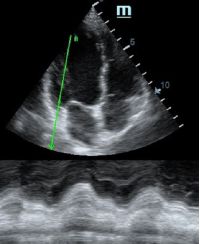

TAPSE - показатель амплитуды движения латеральной части кольца трикуспидального клапана, позволяет количественно и быстро оценить систолическую функцию правого желудочка, норма которого составляет более 17 мм. Главным условием является проведение линии М-режима параллельно стенке правого желудочка в апикальном четырех камерном сечении, что легко достигается при Free Xros.